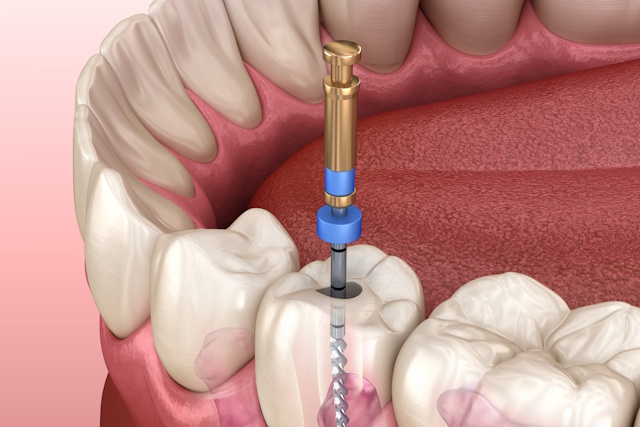

抜髄は、虫歯などで炎症を起こした神経を取り除く最初の処置です。一方、再根管治療は、過去に治療した根管に細菌が再感染し、根の先に膿が溜まった際に行うやり直しの治療です。どちらも再発を防ぐには、マイクロスコープを用いた精密な清掃と、ラバーダム等による徹底した無菌的処置が成功の鍵となります。

歯の寿命を左右する「歯質の保存」を最優先し、アクセスホールを最小限に留めて行う精密根管治療です。マイクロスコープと専用器具を駆使することで、本来の歯の構造を最大限に残しながら、内部の感染を確実に除去します。治療後の破折リスクを大幅に軽減し、歯の強度を維持するための高度な低侵襲アプローチです。